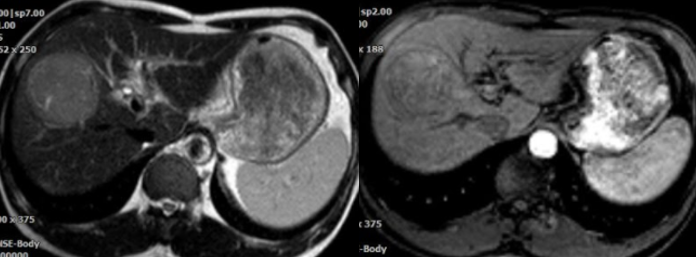

Hình 2: HÌnh ảnh MRI khối u gan trước can thiệp

– BN được làm các xét nghiệm đông máu, chức năng gan, chụp phim CLVT, MRI đánh giá khối u;